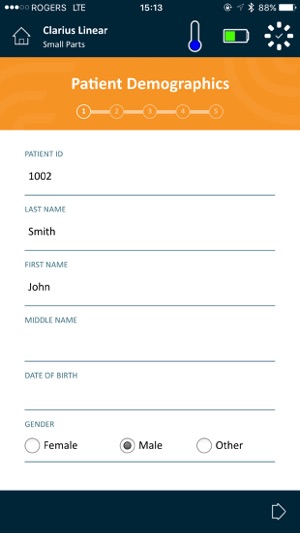

The Clarius Ultrasound App is used by trained medical professionals to operate Clarius Wireless Handheld Ultrasound Scanners. Download the Clarius App to any compatible iOS device(s) and follow the instructions to create a Clarius Cloud account and connect to your Clarius Wireless Scanner(s).

Clarius is the only Handheld Wireless Ultrasound Scanner that doesn’t compromise on image quality. Designed as a Point-and-Shoot Ultrasound™ system, it has automated and optimized gain and frequency settings to capture images quickly. Or you can easily use manual settings to adjust images to your liking.